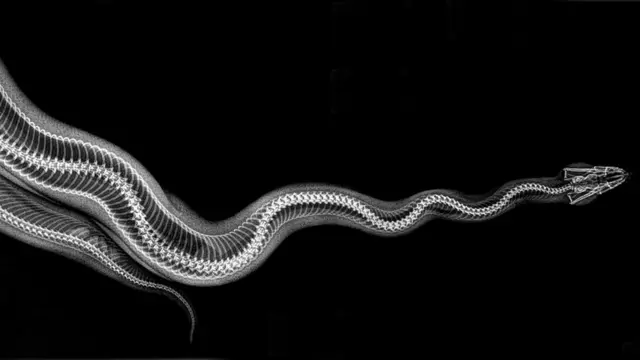

జంతువులను ఎక్స్రే తీస్తే ఎలా కనిపిస్తాయి?

అమెరికాలోని ఓరేగాన్ రాష్ట్రంలో ఉన్న జూ ఒకటి జంతువుల ఎక్స్రే చిత్రాలను పోస్ట్ చేసింది.

జంతువుల ఆరోగ్యాన్ని పరిశీలించేందుకు ఈ జూలో పరీక్షలు నిర్వహిస్తుంటారు. ఆ పరీక్షల సందర్భంగా తీసినవే ఈ చిత్రాలు.

జంతువుల ఆరోగ్యాన్ని పరిశీలించేందుకు ఈ ఎక్స్రే చిత్రాలు చాలా బాగా ఉపయోగపడుతుంటాయని జూ తెలిపింది.